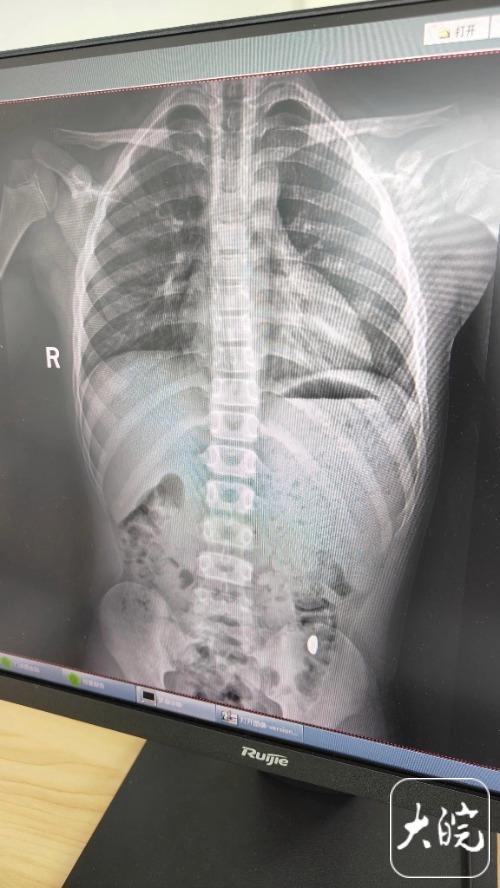

昆山市第五人民醫(yī)院門診病歷單顯示,醫(yī)生在現(xiàn)病史一欄寫著,患兒5天前誤吞約10克黃金,期間解2次大便未發(fā)現(xiàn),目前無腹痛、嘔吐等癥狀,診斷結(jié)果顯示胃內(nèi)有異物。

右下加亮點(diǎn)為金豆。